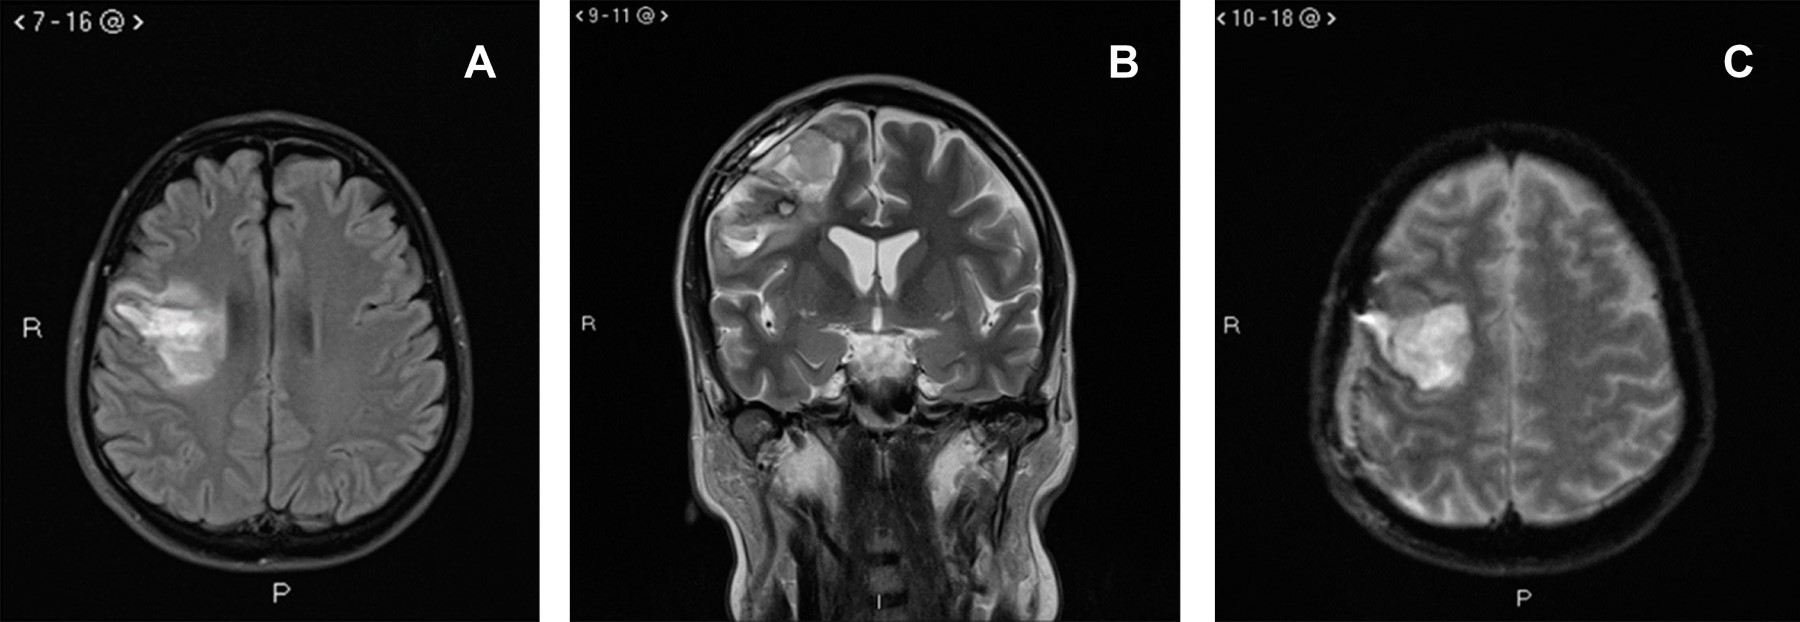

Introduction: systemic lupus erythematosus (SLE) is one of the most common autoimmune diseases; regarding its cerebrovascular effects, most reports indicate subarachnoid hemorrhage and rarely cerebral hemorrhage (CH). Case report: a 44-year-old female presented with non-traumatic cerebral hemorrhage (CH) as the debut of SLE. The patient was treated for CH, and coincidentally, multisystem involvement and severe thrombocytopenia were discovered, which allowed the diagnosis of SLE. Neuroimaging tests did not discover vascular malformations. Conclusions: CH is an uncommon presentation in SLE.

Figure 2